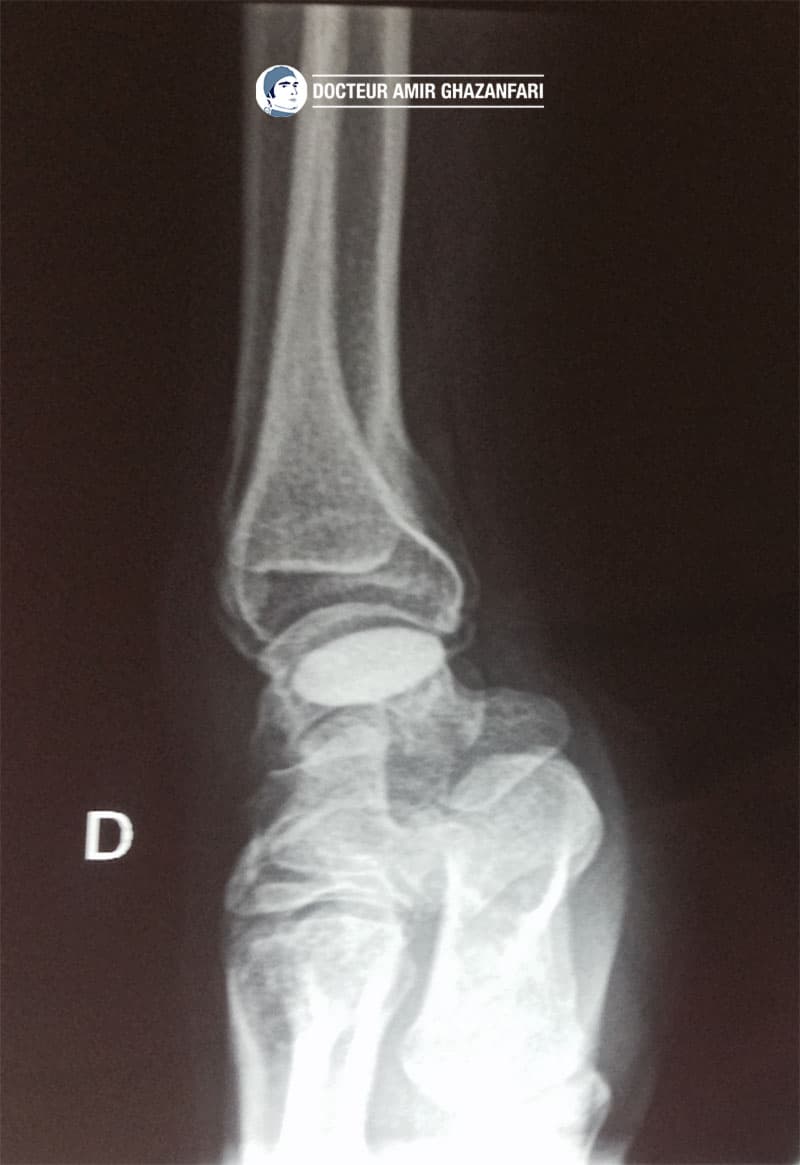

- Les radiographies du poignet permettent de visualiser la pseudarthrose du scaphoïde et une éventuelle arthrose associée (Figure 2).